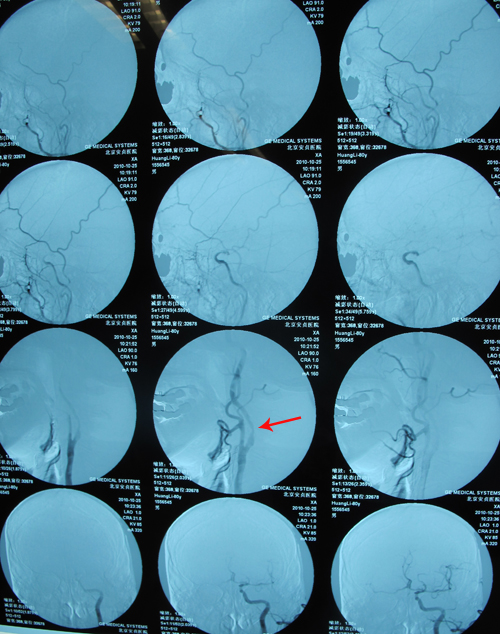

颈动脉CTA:右侧颈内动脉未见显影,左侧颈内动脉近中段管腔重度狭窄,左颈总动脉中远段、左侧颈外动脉近中段、右颈总动脉远段及分叉处管腔中度狭窄,左锁骨下动脉近段、左椎动脉中段管腔轻度狭窄,病因考虑动脉硬化。

头部血管CT造影:右侧颈内动脉颅内段次全闭塞;左侧大脑中动脉水平段以远分支管腔重度狭窄;右椎动脉远段管腔轻度狭窄,病因考虑动脉硬化;右侧大脑半球灌注异常。

脑血管成像(MRA)呈明显动脉硬化改变,以右侧颈内动脉为著。